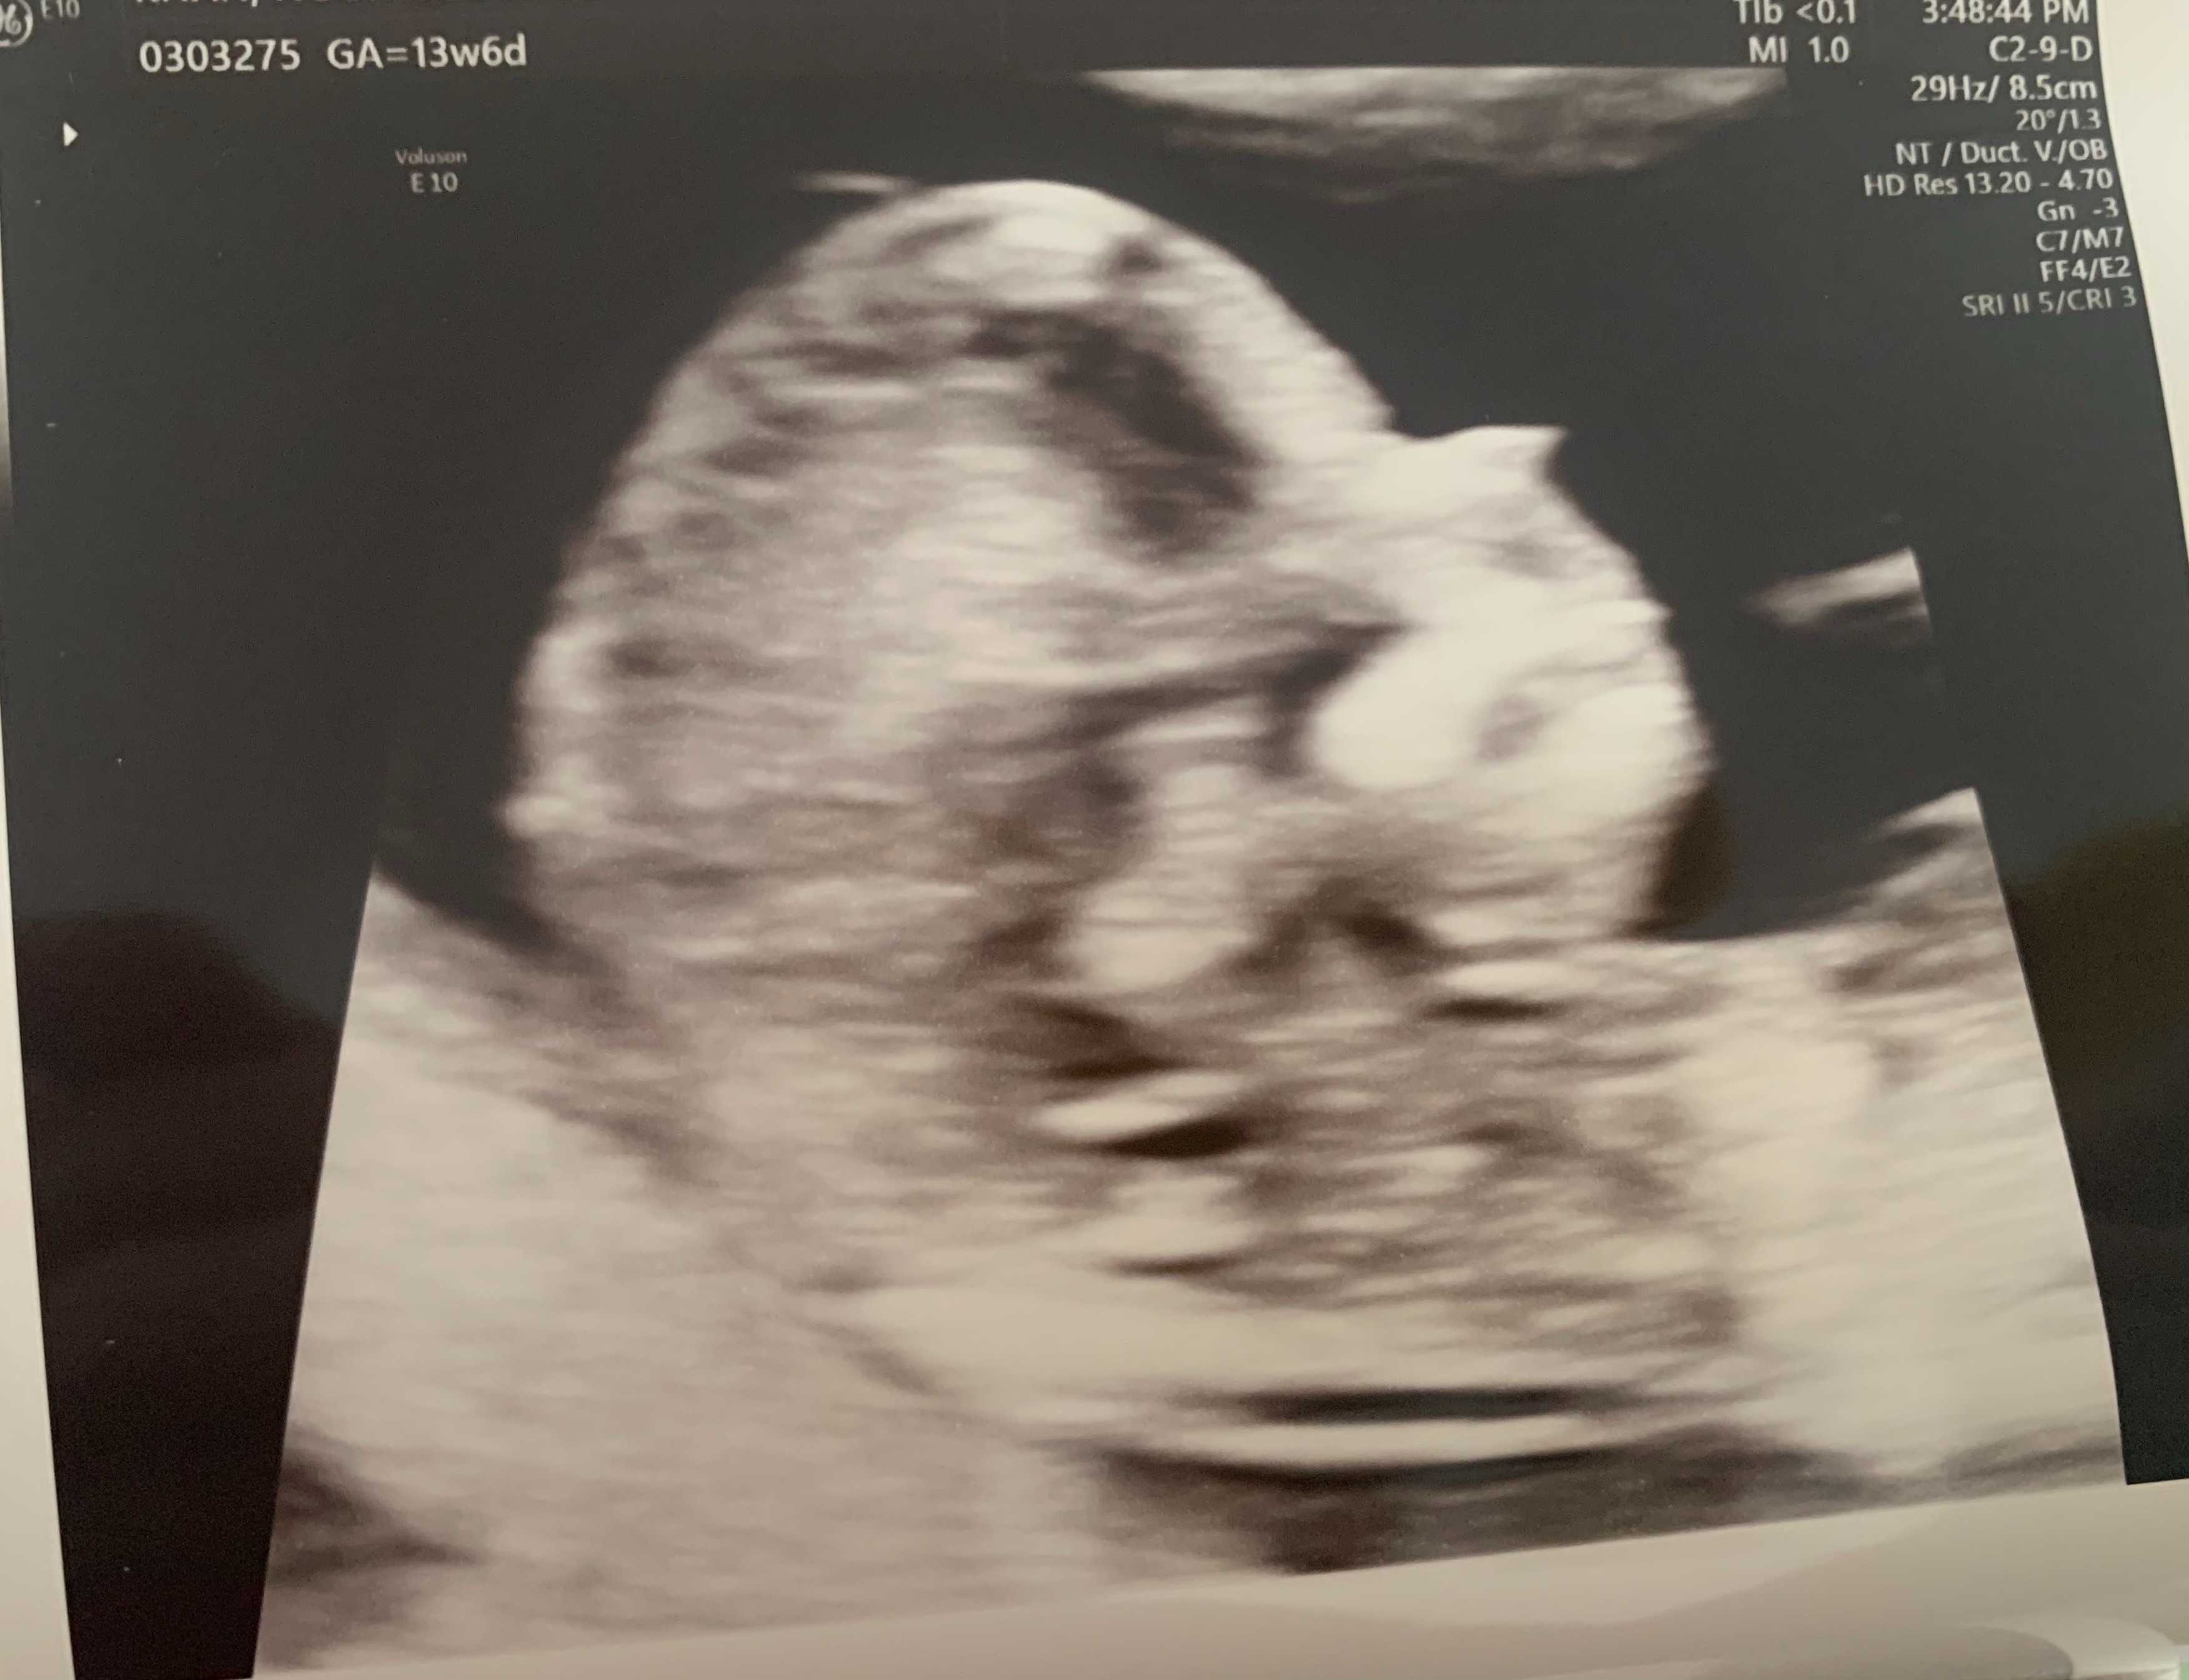

can i have a look at your ultrasound please at first

Dr Aqsa please see the ultrasound pics below

Please check now

Dr Nazish Ali please see the ultrasound reports

Doctors, please see the ultrasound pics below